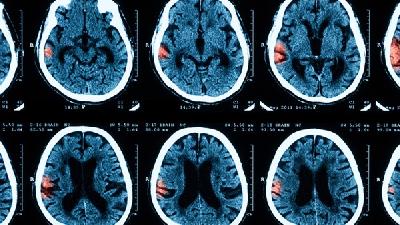

區(qū)分腦癱與發(fā)育遲緩需結(jié)合神經(jīng)影像學(xué)檢查、運(yùn)動(dòng)功能評(píng)估、發(fā)育量表測試及實(shí)驗(yàn)室檢查等綜合判斷。 1、神經(jīng)影像學(xué): 頭...